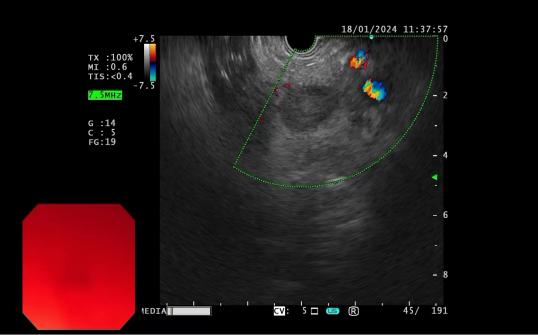

發現內源性低回聲病灶 實時超聲引導下對病灶的細針穿刺活檢

內鏡超聲引導下細針穿刺抽吸術(EUS-FNA):治療對于性質不明的胰腺實性占位性病變;對于經CTMRI或 EUS 等檢查不能確定性質的胰腺囊性病變;對于消化道毗鄰組織中性質不明的占位性病變或淋巴結腫大(如縱隔、上腹部等部位病變);長徑>2cm需要手術切除但具有高手術切除風險,或不能切除的消化道上皮下腫瘤的鑒別診斷。